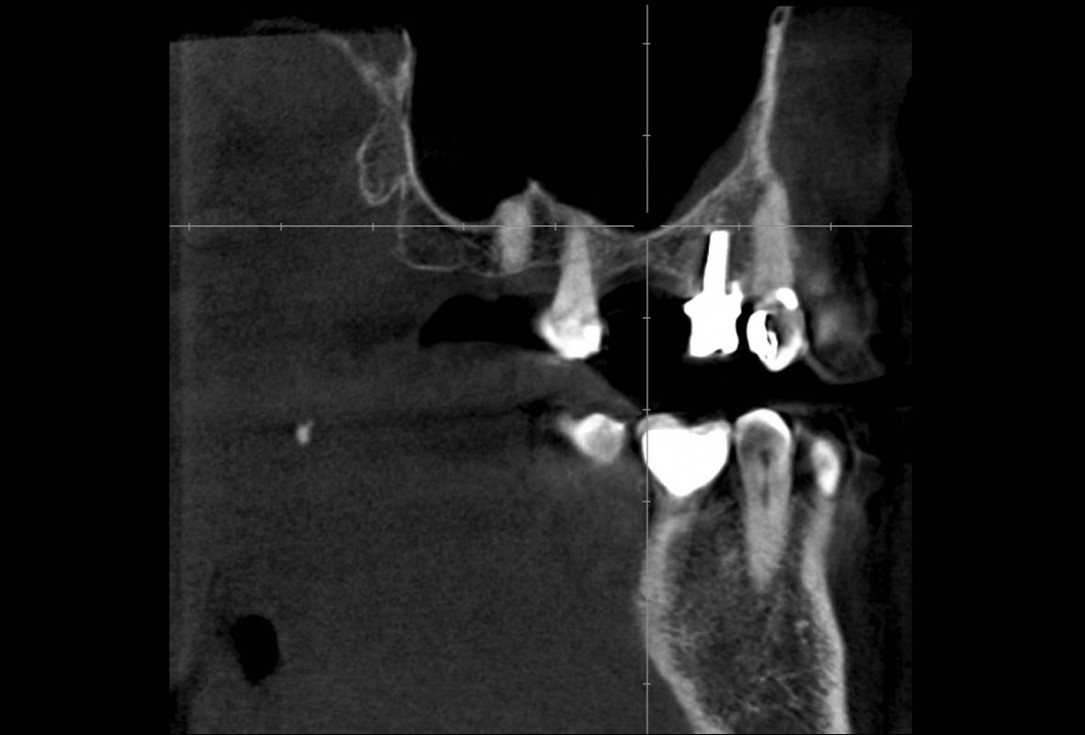

02/35 - CBCT shows maxillary sinus cystMaxillary sinus cyst removal using the Crocodile Technique and subsequent lateral sinus lift - Dres. C. Scognamiglio and A. Perucchi

03/35 - CBCT shows maxillary sinus cystMaxillary sinus cyst removal using the Crocodile Technique and subsequent lateral sinus lift - Dres. C. Scognamiglio and A. Perucchi